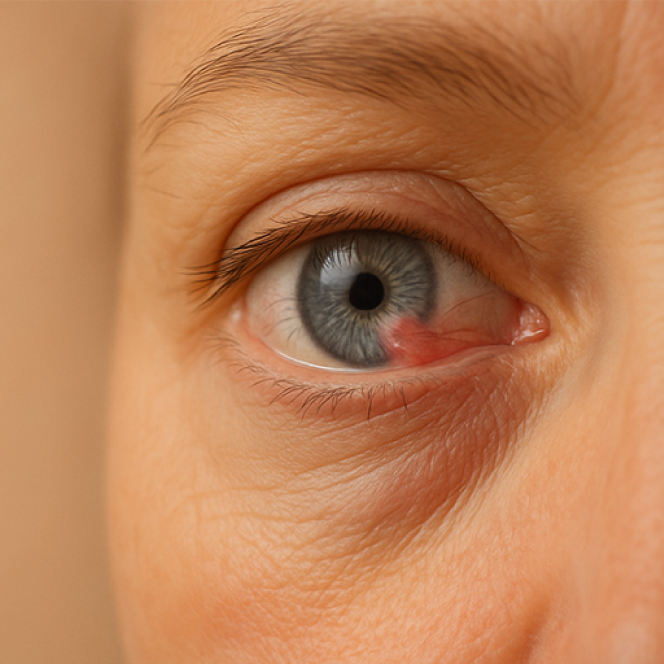

Lo pterigio è una patologia oculare che colpisce la cornea e la congiuntiva, caratterizzata dalla crescita anomala di un tessuto fibrovascolare che può alterare la superficie dell’occhio e, nei casi più avanzati, compromettere la vista e il comfort visivo.

Lo pterigio si presenta come una membrana che si estende dalla congiuntiva verso la cornea, con una colorazione che può variare dal grigiastro al rossastro.

Si sviluppa più frequentemente nella parte nasale dell’occhio e può estendersi progressivamente fino a raggiungere la pupilla, compromettendo la visione.

Nei primi stadi della malattia, il paziente può non avvertire particolari disturbi, ma con il tempo possono insorgere irritazione, arrossamento, infiammazione cronica, secchezza oculare e persino disturbi visivi dovuti alla deformazione della cornea.

Nei casi più avanzati, lo pterigio può limitare la motilità oculare, creando un disagio funzionale oltre che estetico.